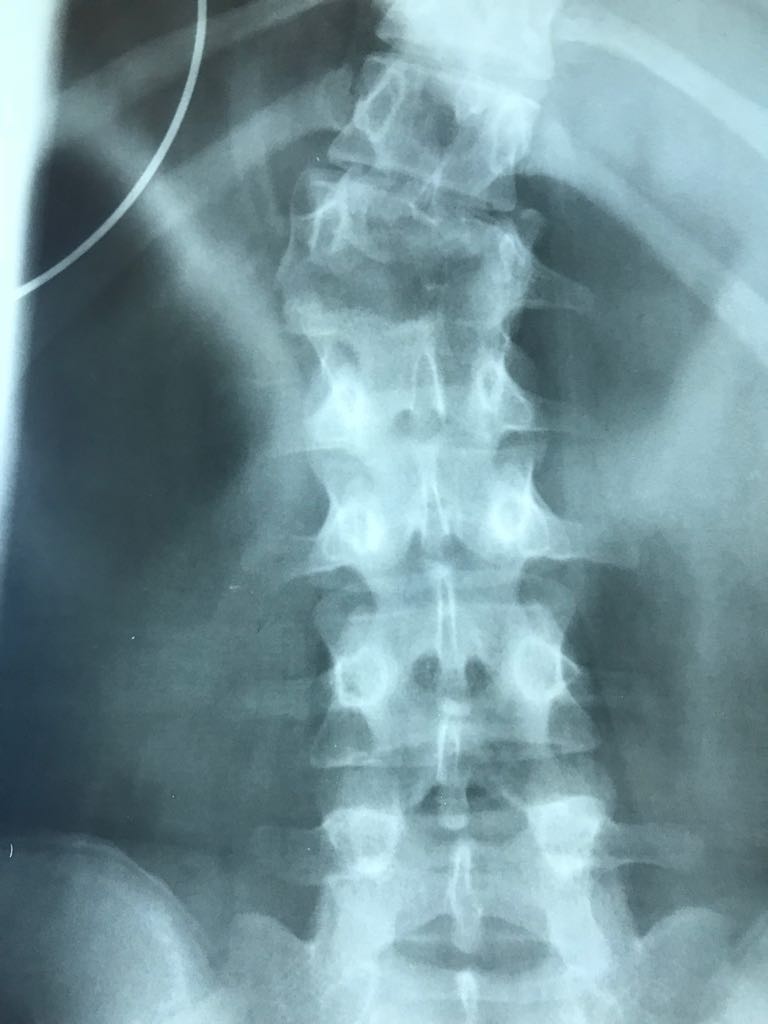

Ameliyat Öncesi